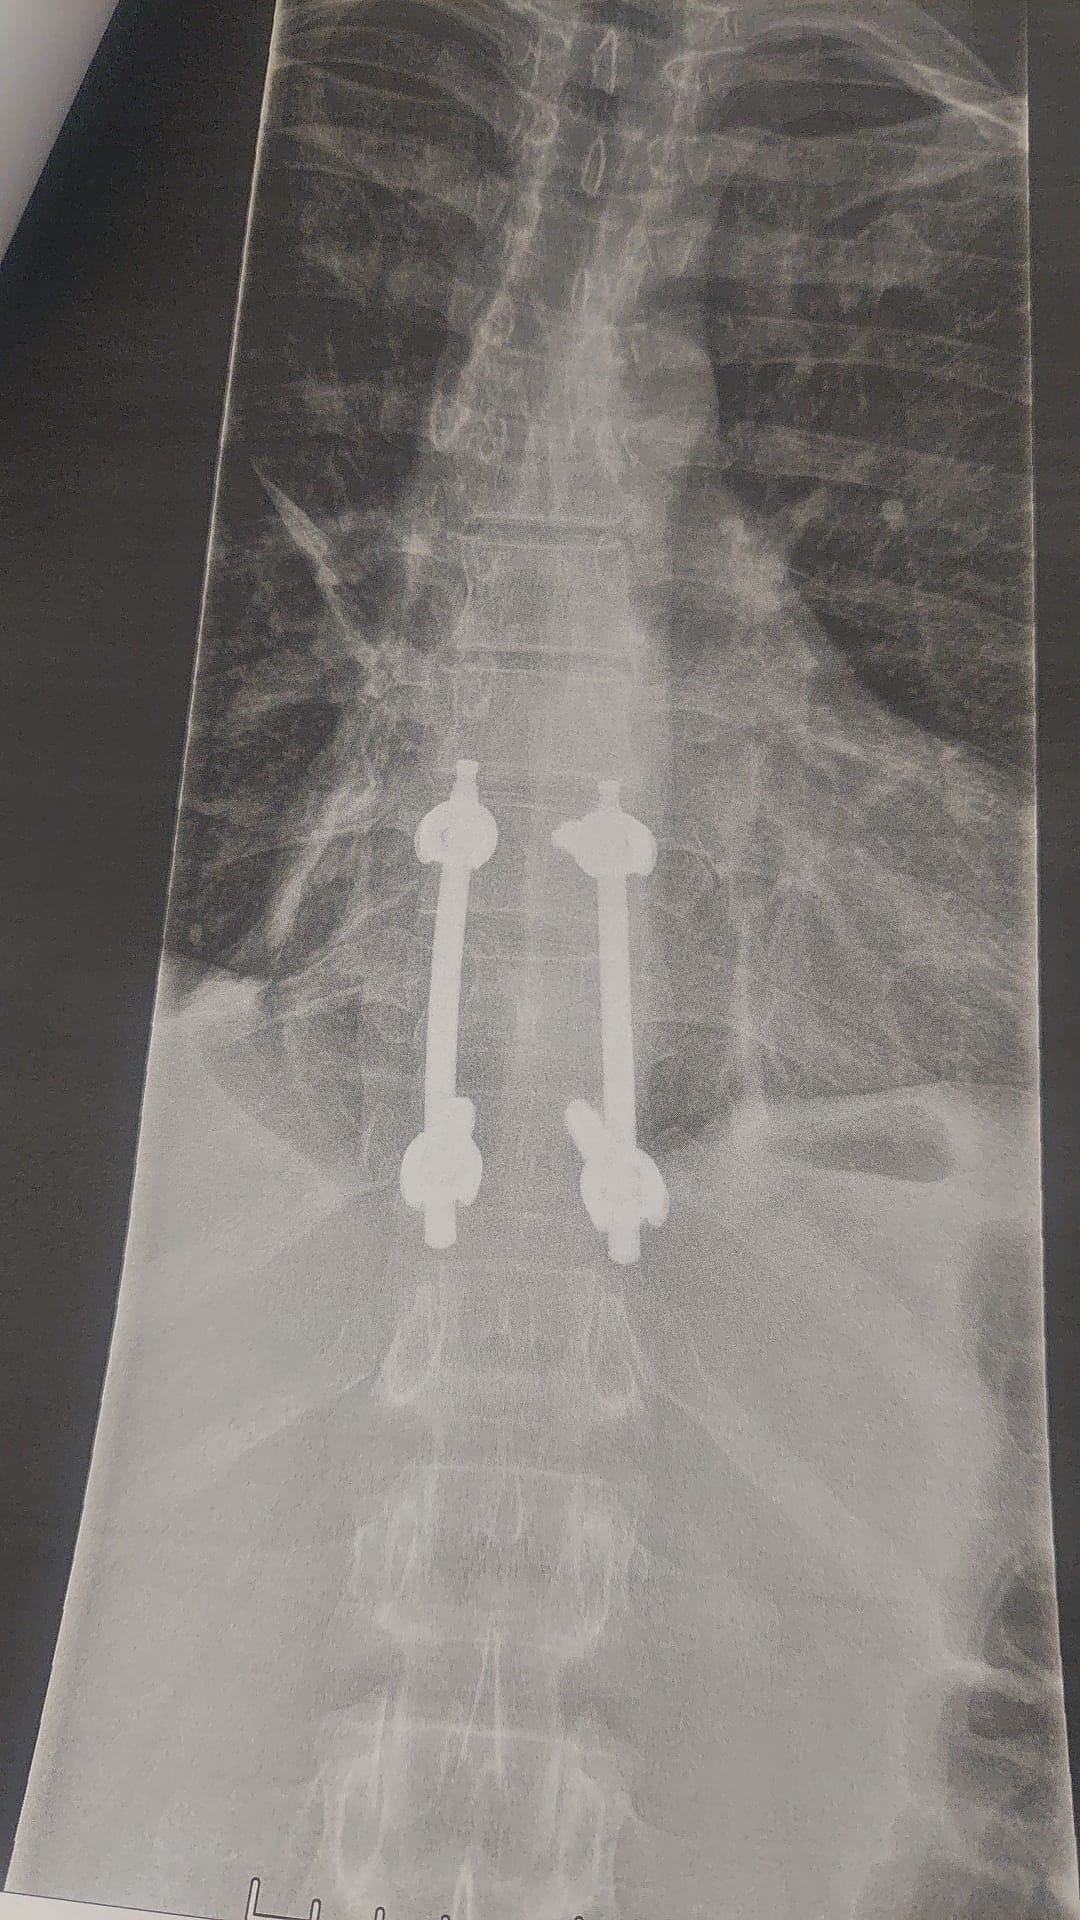

We’re reaching out to ask for your support for Jamie, a passionate and talented motorbike racer who recently suffered a crash at Snetterton Circuit at the 4th round of British Superbikes. Jamie fractured his back in three places which required surgery to make stable enough to ensure no neuromuscular issue. He has some numbness in his right arm but have been assured this will return in its own time. The surgery was successful but we all know the road ahead will be long and tough.